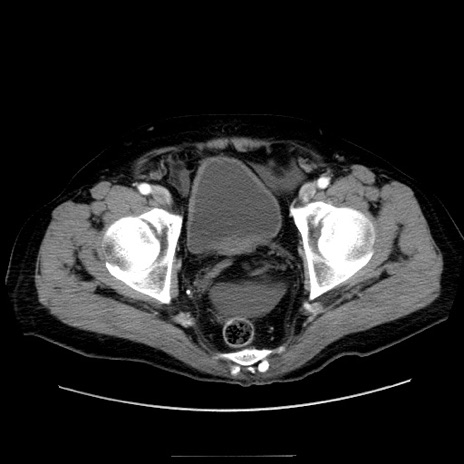

症例30(横断像)

【症例】80歳代男性

【主訴】臍周囲痛

【現病歴】約6時間前から臍下部痛が出現。次第に腹部膨隆・背部痛も生じてきたため来院。背部痛の場所は変化しない。

【身体所見】意識清明、BT 36.3℃、BP  131/87mmHg、P 87bpm、SpO2 100%(RA)、臍周囲自発痛・圧痛あり、反跳痛なし、自発痛部位に一致して板状硬あり、腹部膨隆、腸雑音減弱、CVA tenderness両側陰性。

【データ】WBC 19600、CRP 0.33